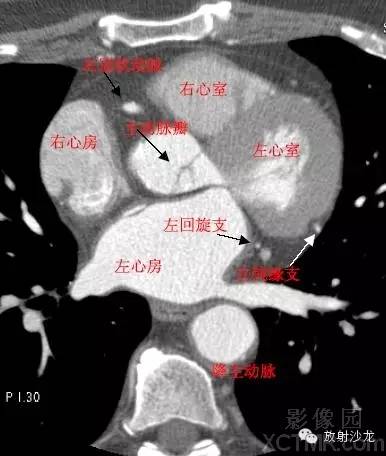

LA -Left Atrium左心房

RA -Right Atrium右心房

LV -Left Ventricle左心室

RV -Right Ventricle右心室

LCX -Left Circumflex Artery左回旋支

PDA -Posterior Descending Artery后降支

GCV–Great Cardiac Vein心大静脉